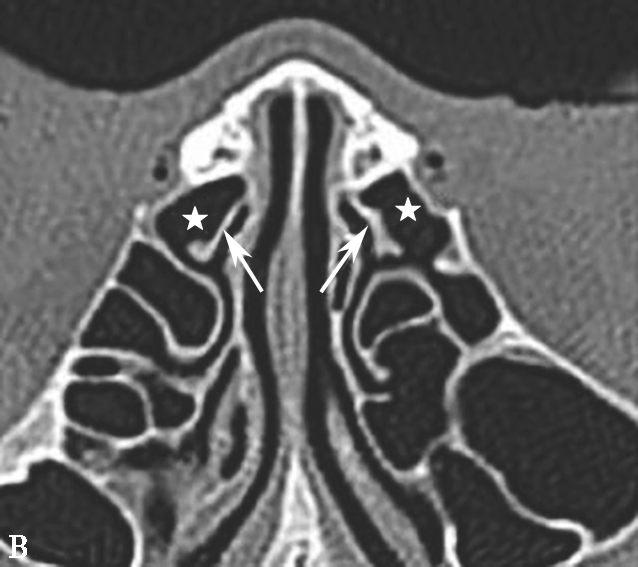

鼻丘气房位于筛漏斗的前上部,与泪骨、上颌骨、筛骨、额骨、鼻骨关系密切。是由筛漏斗直接发展而来。鼻丘气房通常位于额窦底的前部,构成额隐窝的前壁,大小不一,过大、过多可妨碍额窦引流,引起额窦炎。鼻丘气房和钩突眶内壁附着点之间的关系非常密切。当钩突与眶内壁没有附着点时,鼻丘气房不存在;当钩突与眶内壁仅有一个附着点时,鼻丘气房存在;当钩突与眶内壁有两个及以上附着点时,形成上下两个气房,在冠状面观察,偏下的气房称为鼻丘气房,偏上的气房称为额气房,两者内壁均由钩突构成(图1-3-1)。

图1-3-1 鼻丘气房及额气房CT解剖

A~C.鼻丘气房(五角星),额气房(星),钩突(白箭),筛骨纸板(箭头)